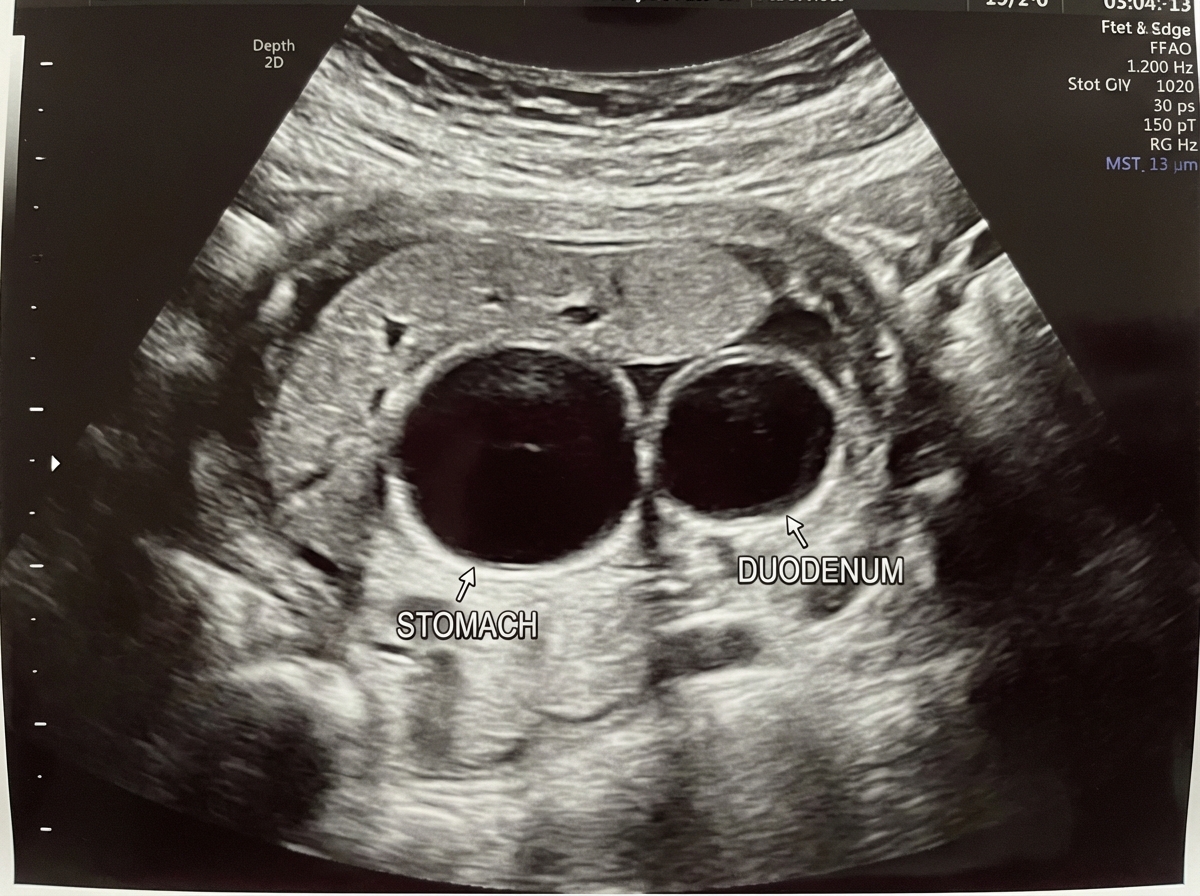

In which genetic condition is this most likely to be seen?

Explanation: ***Trisomy 21*** - The **double bubble sign** (duodenal atresia) on prenatal ultrasound has a strong association with **Down syndrome**, occurring in approximately **30%** of cases. - **Trisomy 21** is the most common viable autosomal trisomy and frequently presents with gastrointestinal anomalies including **duodenal atresia**. *Trisomy 16* - **Most common trisomy** in spontaneous miscarriages but is **not compatible with life** beyond early pregnancy. - Does not typically present with duodenal atresia as affected fetuses do not survive to term. *Monosomy X* - **Turner syndrome** classically presents with **cystic hygroma**, **coarctation of aorta**, and **webbed neck** on prenatal imaging. - Gastrointestinal anomalies like duodenal atresia are **not characteristic** features of this condition. *Trisomy 13* - **Patau syndrome** typically presents with **holoprosencephaly**, **polydactyly**, and severe central nervous system malformations. - While gastrointestinal anomalies can occur, **duodenal atresia** is not a classic association with this condition.